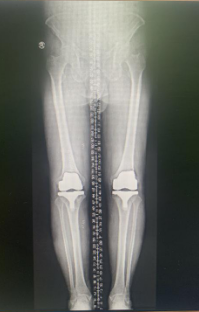

左图:左腿 (术前),右图:左膝(换关节后)

右膝术后